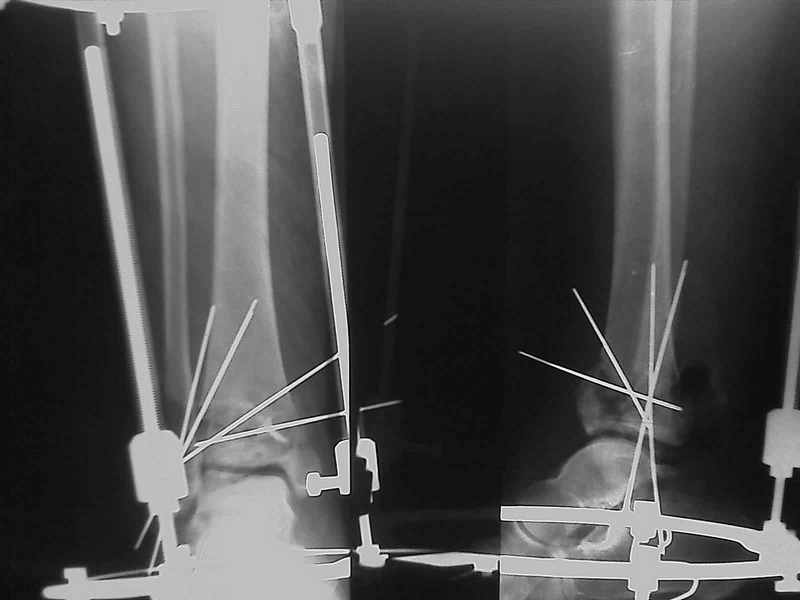

Снова приветствую вас, коллеги. К моменту вступления в обсуждение аксакалов, операция была, увы, выполнена(31.10.07.) Начали с доступа к наружной лодыжке, произвели ее фиксацию спицами, развернули кусок заднего края, наложили дистрактор, затем произвели дистракцию, фиксацию спицами дистального эпиметафиза б/бк,Рентгено-контроль. синтез наружной лодыжки 1/3пластиной. из двух коротких разрезов сформирован канал под медиальную тибиальную пластину LCP. Края ран ушиты без натяжения. Прочувствовать жесткость фиксации винтами с угловой стабильностью не удалось, поэтому дистрактор оставлен на энное время.

На представленных R-снимках не окончательный вид после остеосинтеза. Дистальная опора давила на стопу, пришлось ее сместить проксимально, в рез-те чего, она закрыла щель сустава, последние снимки не информативны.

У меня вопрос. Почему проксимальный фрагмент с медиально стороны фиксированк плате всего одним болтом.

Нижний винт, похоже, длинноват.

Дистальные винты как-то чуть не все идут не в дистальные отломки, а в зону перелома. И действительно, присоединяюсь к вопросу Якова - в диафизе так и оставили 1 винт?